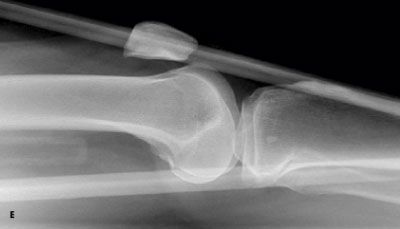

Outcome of this case. The patient'sdislocation was reduced externally.A frontal radiograph of the kneeobtained after the reduction showsnormal alignment of the patella andthe distal femur (D). This is confirmedby a post-reduction lateral view (E).At 3 months, the patient has not hada recurrence.